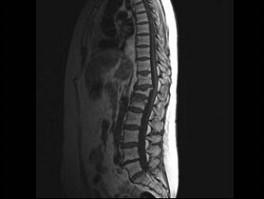

问题 男,65岁,背痛半月余,请结合影像学检查,选出最可能的诊断 ( )

选项 A、骨质疏松性椎体骨折 B、脊椎退行性变 C、脊柱转移瘤 D、化脓性脊柱炎 E、脊椎结核

答案 A